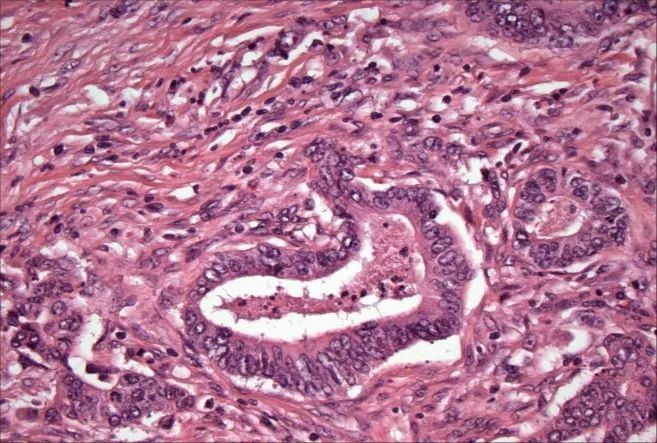

▲結(jié)腸癌示意圖,可清晰看到癌細胞呈圈狀結(jié)構(gòu)▲結(jié)腸癌示意圖,可清晰看到癌細胞呈圈狀結(jié)構(gòu)